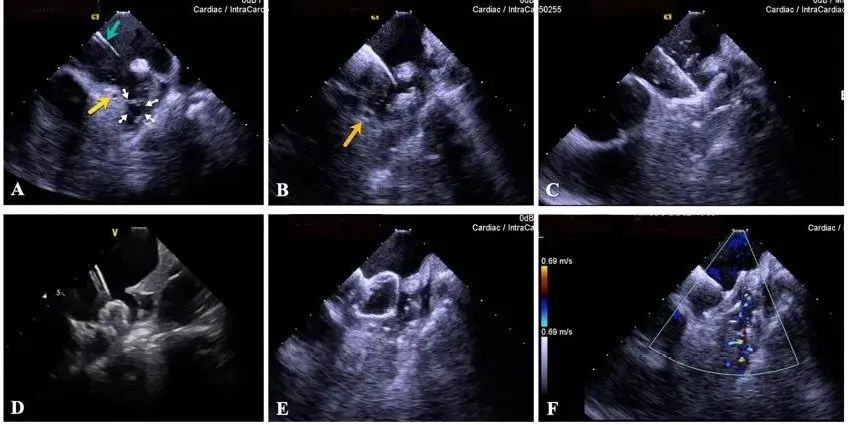

一種與心導(dǎo)管檢查相結(jié)合的超聲心動圖診斷新興技術(shù),通過將超聲探頭置于心腔內(nèi)部,發(fā)射并接收超聲信號,來精確獲取心臟解剖結(jié)構(gòu)、心臟血流動力學(xué)等信息的實時成像。與其他影像技術(shù)相比,ICE技術(shù)具有操作簡單、無輻射、安全性高、手術(shù)效率高、實用等優(yōu)勢,ICE在很大程度上有望取代經(jīng)食道超聲心動圖(TEE),成為電生理和結(jié)構(gòu)性心臟病領(lǐng)域的理想成像方式。

目前ICE技術(shù)已被應(yīng)用于左心耳封堵、房顫射頻消融、二尖瓣成形、房間隔缺損封堵等多種心臟介入手術(shù),應(yīng)用場景主要圍繞心臟電生理、結(jié)構(gòu)性心臟病等領(lǐng)域,目前以電生理應(yīng)用為主。數(shù)據(jù)顯示,我國結(jié)構(gòu)性心臟病介入器械市場規(guī)模已從2017年的4億元增長至2021年的20億元,年復(fù)合增長率達(dá)48.3%;預(yù)計到2025年,該市場規(guī)模將達(dá)到104億元,可以預(yù)見ICE市場規(guī)模也將同步高速增長,未來市場發(fā)展空間廣闊。

心腔內(nèi)超聲(ICE)技術(shù)壁壘極高,國內(nèi)主要廠商核心部件仍舊為進(jìn)口,集成了超聲和圖像處理最前端技術(shù),包括超聲探頭、線纜、軟件成像算法等,是當(dāng)前內(nèi)窺超聲方向最具挑戰(zhàn)的領(lǐng)域。ICE的應(yīng)用經(jīng)歷了2D平面成像、3D三維立體成像、以及4D的實時三維立體成像階段。